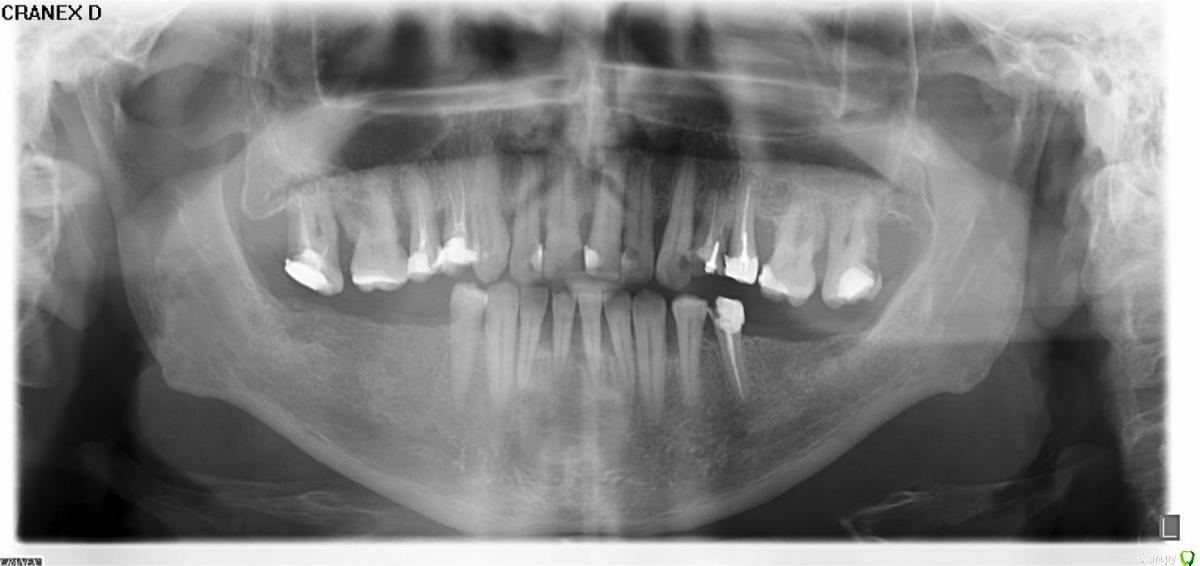

Гарриевич Опубликовано 20 мая, 2015 Поделиться Опубликовано 20 мая, 2015 (изменено) 1 - профессиональная гигиена полости рта, с участием пародонтолога2- удаление 17 16 26 27 и 25(под вопросом) зубов3- перелечивание 15 14 24 25 и 35(под вопросом) зубов4- протезирование коронками 15 14 24 25 35 зубов5- прямая или непрямая реставрация 13 12 11 21 22 23 зубов6- или имплантация а области 45 46 47 36 37 зубов на нижней челюсти и 17 16 26 27 зубов верхней челюсти (для планирования имплантации нужен снимок КТ) или бюгельный съемный протез на верхнюю и на нижнюю челюсть с перелними нижними зубами разговор тоже только после КТ Изменено 20 мая, 2015 пользователем Гарриевич 2 Ссылка на комментарий